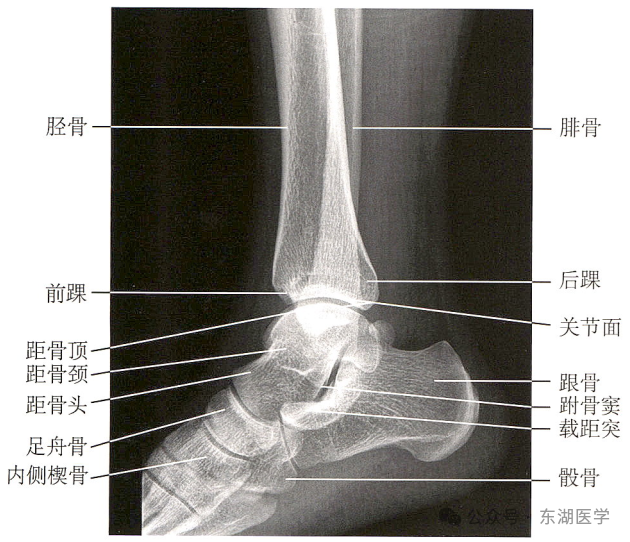

足以骨骼为支架,包括7块跗骨、5块跖骨、14块趾骨,彼此间借关节和韧带相连接。

成人足正、斜位X线解剖

1. 甲粗隆;2.踇趾远节趾骨;3. 趾间关节;4.踇趾近节趾骨;5. 第1跖骨头;6. 籽骨;7. 第1跖骨干; 8. 第1跖骨基底部;9. 内侧楔骨;10. 中间楔骨;11. 外侧楔骨;12.足舟骨;13. 距骨;14.远节趾骨;15.中间趾骨;16. 近节趾骨;17. 跖趾关节;18.第2跖骨基底部;19.第3跖骨基底部;20.第4跖骨基底部;21.第5跖骨基底部;22.骰骨;23. 跟骨